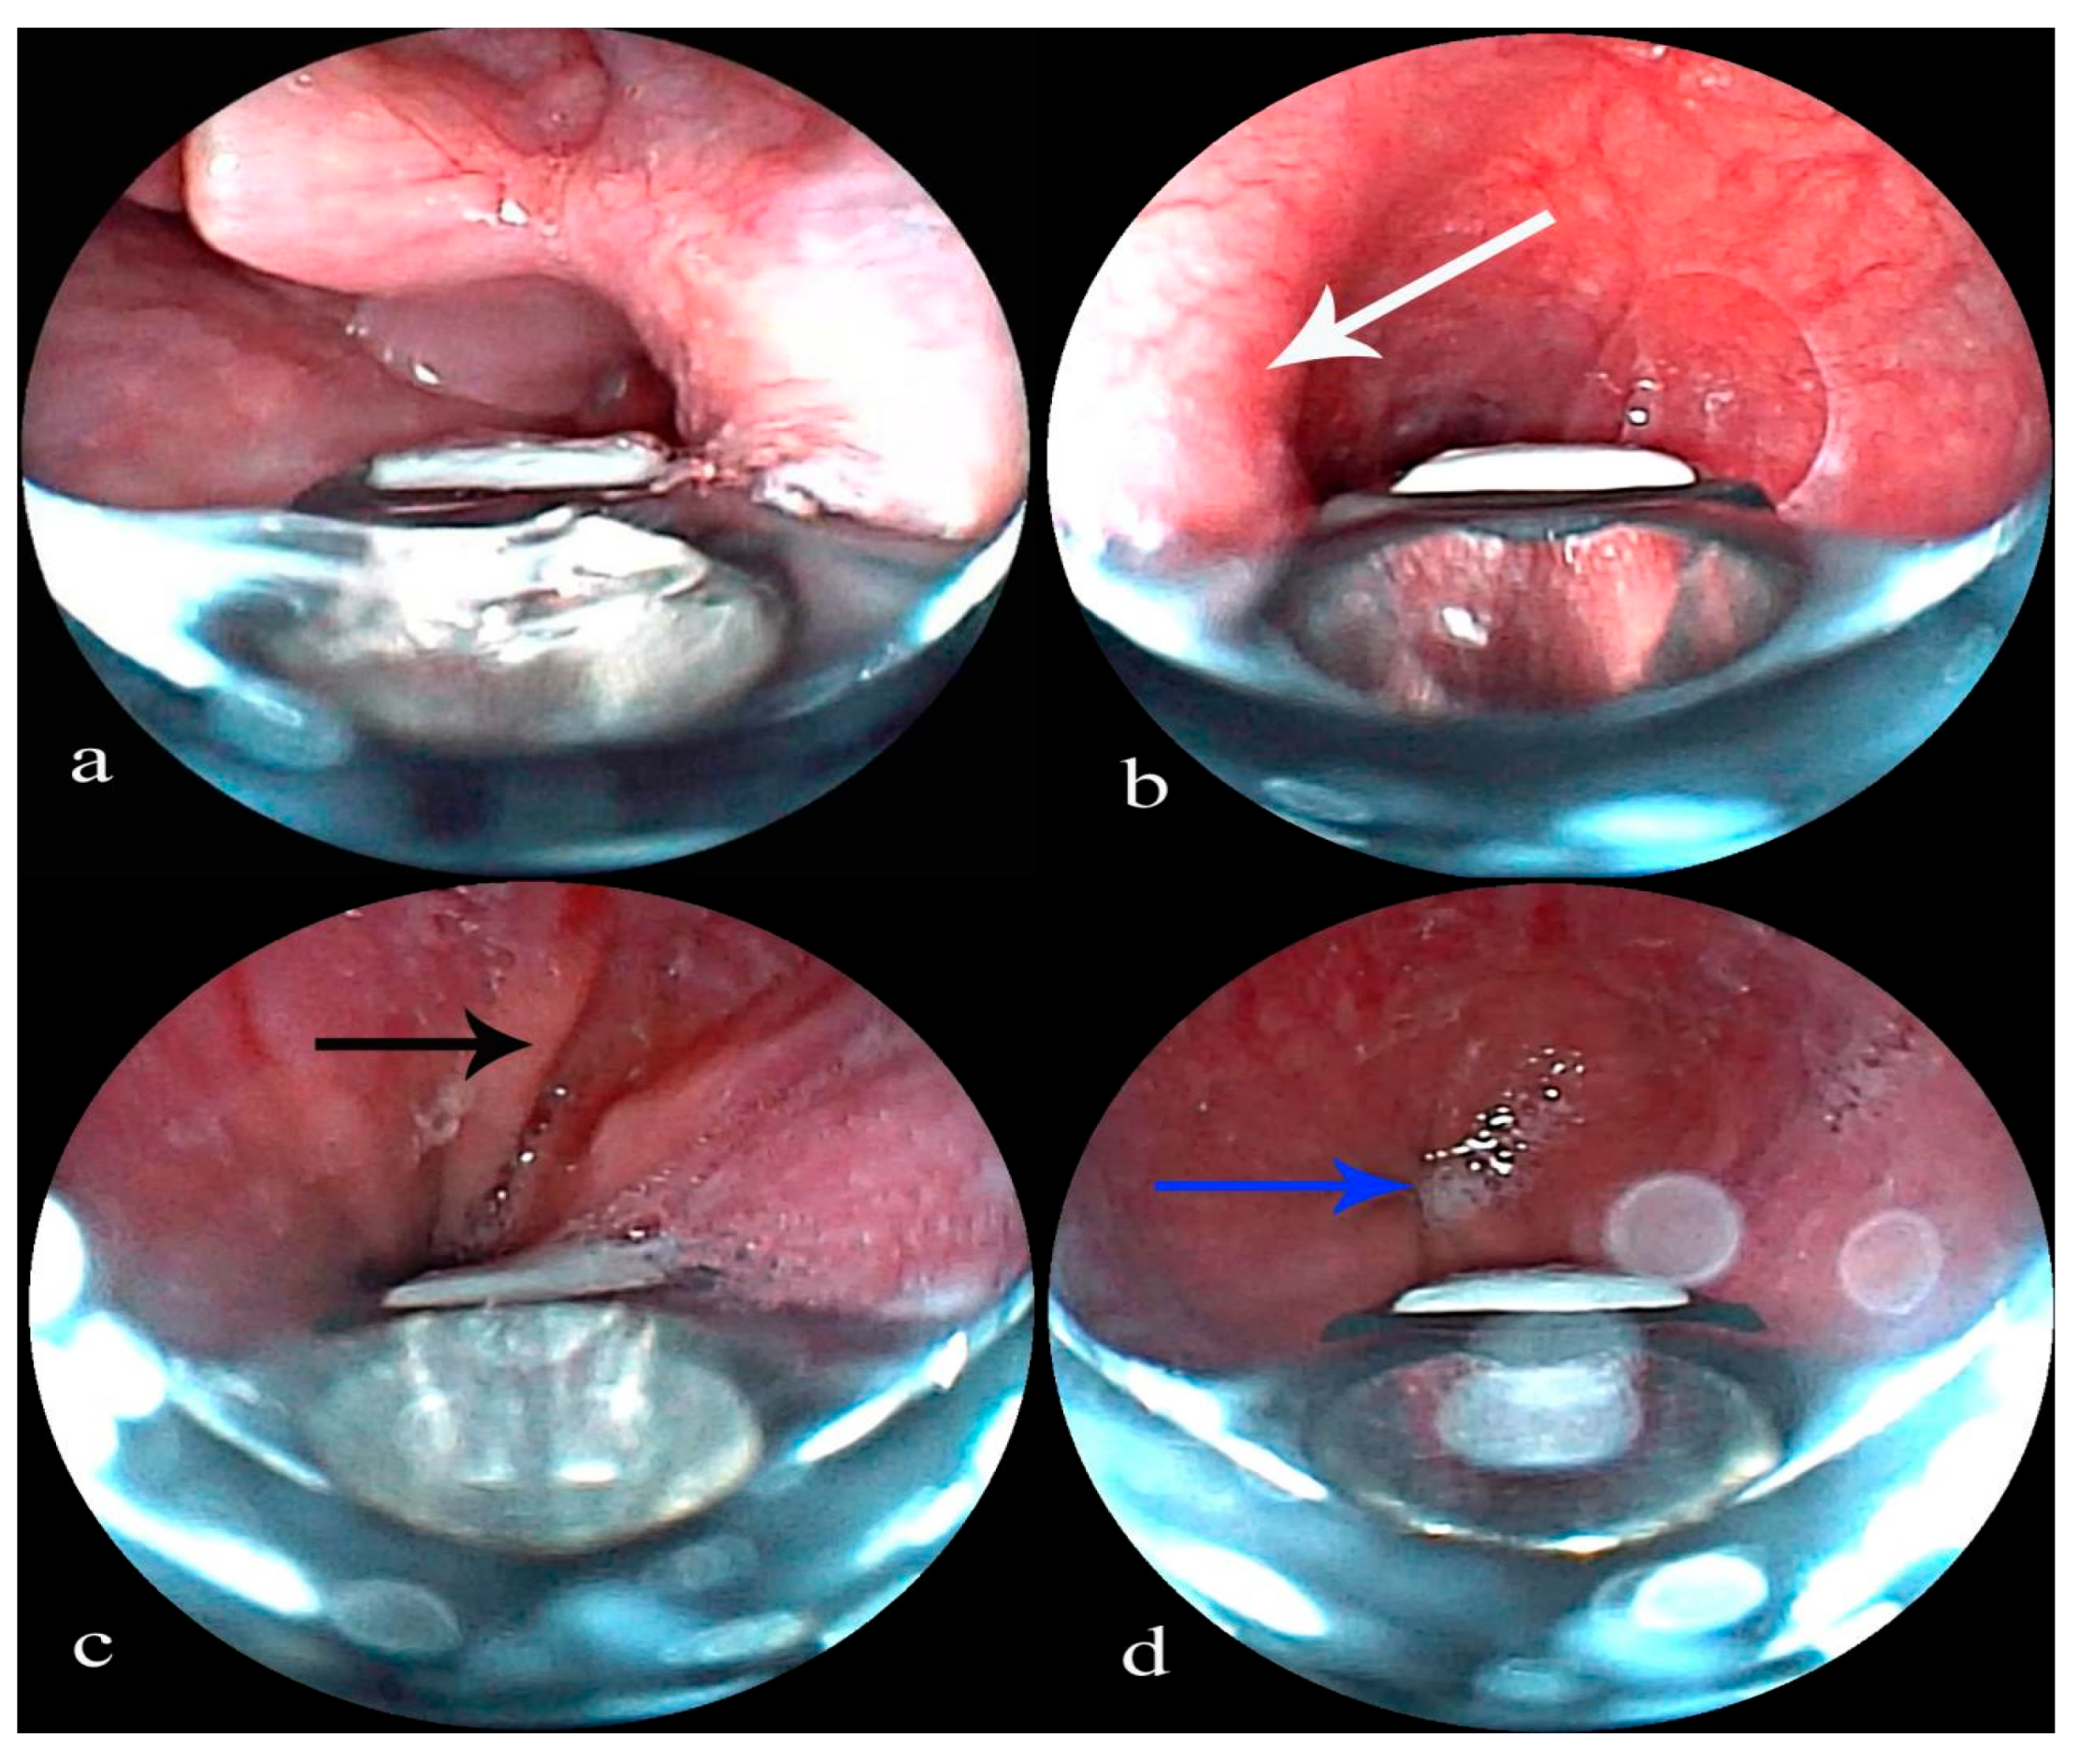

Insertion and Esophageal Approach: Oxygen is administered via a nasal cannula, and the patient is carefully positioned in a slightly lateral decubitus position [6]. An EBUS bronchoscope is skillfully inserted orally, passed beneath the glottis, and then directed into the esophagus (Figure 1a). The unique anatomical features visible during esophageal endoscopy serve as reliable markers for the bronchoscope’s location. These markers include the following: a rhythmic protrusion on the lateral aspect of the middle esophagus, corresponding to aortic pulsation, which indicates an aortic arch impression (Figure 1b); the Z-line, which is clearly defined at the junction between the lower esophagus and the gastric cardia (Figure 1c,d); and a constriction at the site where the esophagus passes through the diaphragmatic hiatus.

Figure 1. (a) An EBUS bronchoscope is advanced below the glottis into the esophagus. (b) Aortic arch impression (white arrow). (c) The Z-line (black arrow). (d) Gastric cardia (blue arrow).